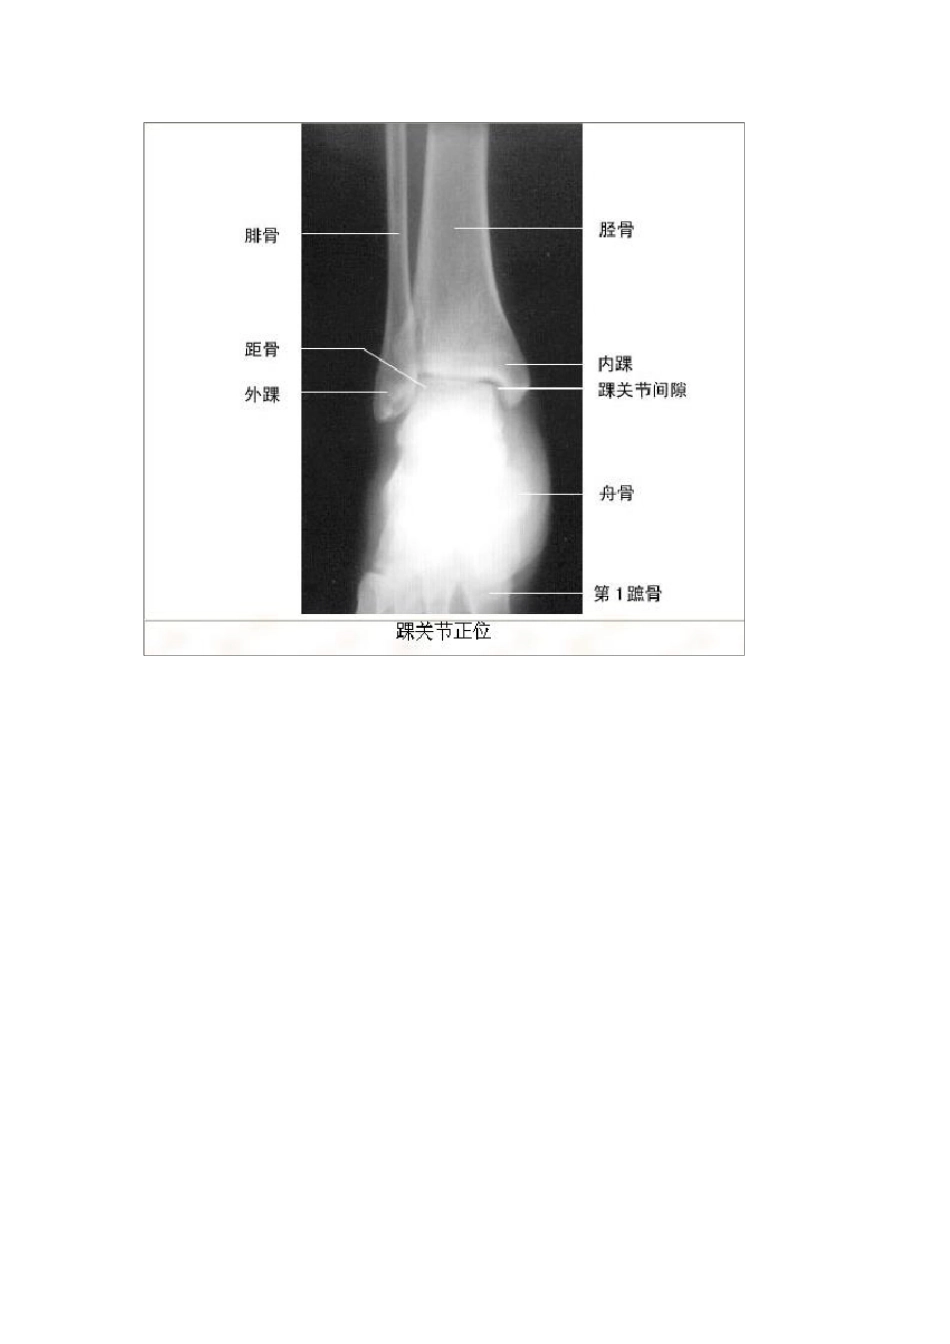

影像解剖影像图谱珍藏版